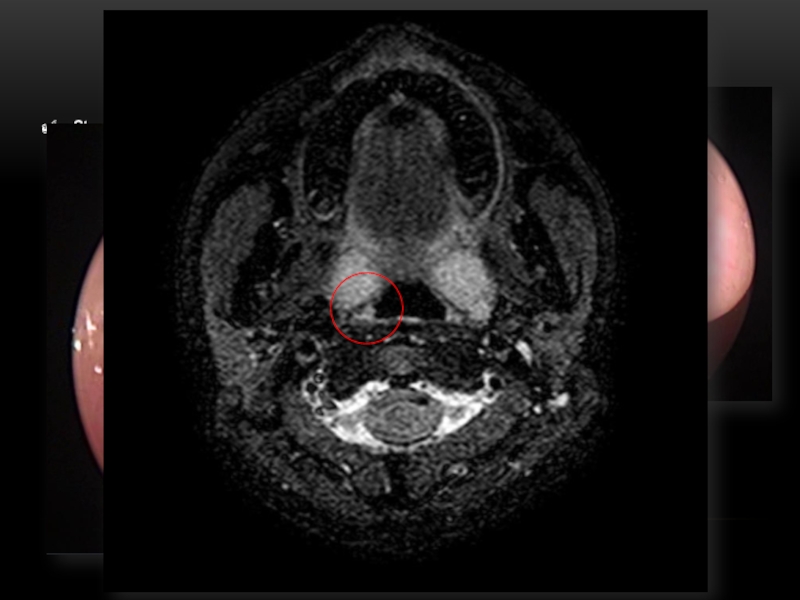

Слайд 13АНОМАЛИИ РАЗВИТИЯ ВНУТРЕННЕЙ СОННОЙ АРТЕРИИ

Пациент Ш., 15 лет.

Перегиб правой

a. carotis interna, расположенный на уровне средней трети небной миндалины.

Петля левой a. carotis interna, располагающаяся выше уровня верхнего полюса небной миндалины.